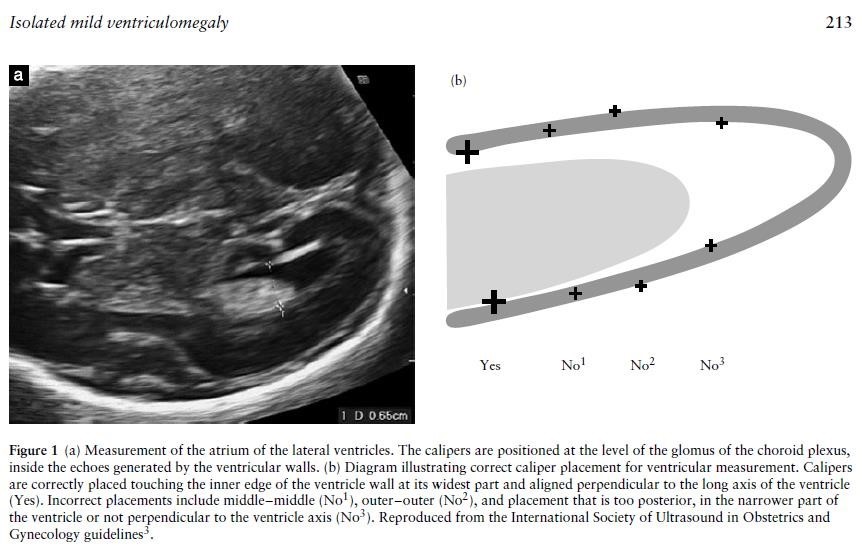

Accurate measurement of the ventricles is important in both defining ventriculomegaly and also assessing progression. The fetal head should be scanned in the axial plane at the level of the frontal horns and the cavum septum pellucidum (CSP) (the same level at which a head circumference is taken), at an appropriate magnification that the head fills the screen. The callipers should be placed at the internal margins of the atrial walls at the level  of the parietal occipital groove and the glomus of the choroid plexus, perpendicular to the axis of the ventricle.